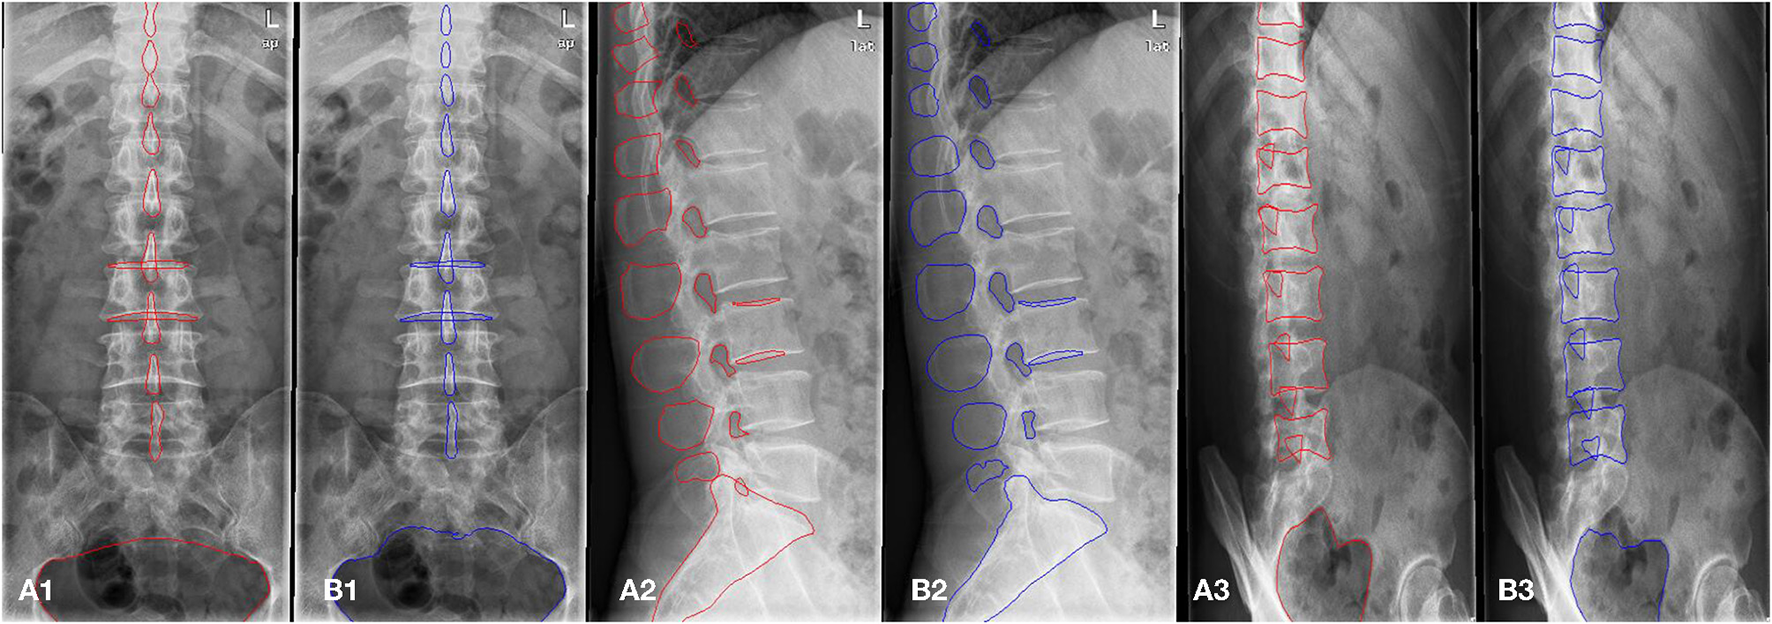

Figure 2

(A1,A2) Shows images of anteroposterior position. (A1) Shows qualified image. (A2) Shows unqualified image (1. Too many thoracics vertebrae; 2. Not centered and bent). (B1,B2) Shows images of lateral position. (B1) Shows qualified image. (B2) Shows unqualified image (1. Not clear; 2. Double shadow; 3. The left and right edges do not overlap). (C1,C2) Shows images of oblique position. (C1) Shows qualified image. (C2) Shows unqualified image (1. Excessive and foreign bodies in the chest; 2. Insufficient angle; 3. Less at the bottom).

In this study, the lumbar spine x-ray images of 1,070 patients were evaluated by three experienced radiologists. The qualified x-ray images were those that met the criteria listed above for each radiograph position. Figure 2 presents examples of qualified and unqualified lumbar spine x-ray images.

Figure 2A1 shows the standard anteroposterior view.

Figure 2B1 shows the standard lateral view.

Figure 2C1 shows the standard oblique view.